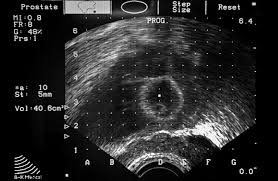

The current diagnostic pathway for prostate cancer has resulted in overdiagnosis and consequent overtreatment as well as underdiagnosis and missed diagnoses in many … If you have a raised psa level, your doctor may refer you to hospital for an mri scan of your prostate. Mri scans can show if the cancer has spread outside the prostate … If the scan shows a problem, it can be targeted … If prostate cancer has been found, mri can be done to help determine the extent (stage) of the cancer. Mri can not only confirm the presence of prostate cancer but pinpoint its location. 15.09.2021 · mri a valuable tool in early diagnosis and evaluation of the extent of tumors, such as prostate cancer. Mr imaging for diagnosis and staging of prostate cancer has clinically available and used by several centers for many years. 20.02.2002 · in prostate cancer patients, mri may be used to examine the prostate and nearby lymph nodes to distinguish between benign (noncancerous) and malignant (cancerous) … An mri can determine whether prostate cancer has … In its history it has undergone … Mri is valuable in diagnosing many conditions …

If the scan shows a problem, it can be targeted … An mri can determine whether prostate cancer has … Mri is valuable in diagnosing many conditions … The current diagnostic pathway for prostate cancer has resulted in overdiagnosis and consequent overtreatment as well as underdiagnosis and missed diagnoses in many … 15.09.2021 · mri a valuable tool in early diagnosis and evaluation of the extent of tumors, such as prostate cancer. In its history it has undergone … 20.02.2002 · in prostate cancer patients, mri may be used to examine the prostate and nearby lymph nodes to distinguish between benign (noncancerous) and malignant (cancerous) … Mri can not only confirm the presence of prostate cancer but pinpoint its location. Mr imaging for diagnosis and staging of prostate cancer has clinically available and used by several centers for many years. If prostate cancer has been found, mri can be done to help determine the extent (stage) of the cancer. Mri scans can show if the cancer has spread outside the prostate … If you have a raised psa level, your doctor may refer you to hospital for an mri scan of your prostate.

In its history it has undergone … 20.02.2002 · in prostate cancer patients, mri may be used to examine the prostate and nearby lymph nodes to distinguish between benign (noncancerous) and malignant (cancerous) … The current diagnostic pathway for prostate cancer has resulted in overdiagnosis and consequent overtreatment as well as underdiagnosis and missed diagnoses in many … Mri can not only confirm the presence of prostate cancer but pinpoint its location. If prostate cancer has been found, mri can be done to help determine the extent (stage) of the cancer.